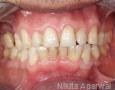

Pictures

Baseline